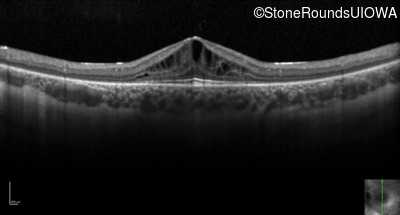

Optical Coherence Tomography - Left - 20/40 -1

Exemplar / OCT Stack

OCT Stack